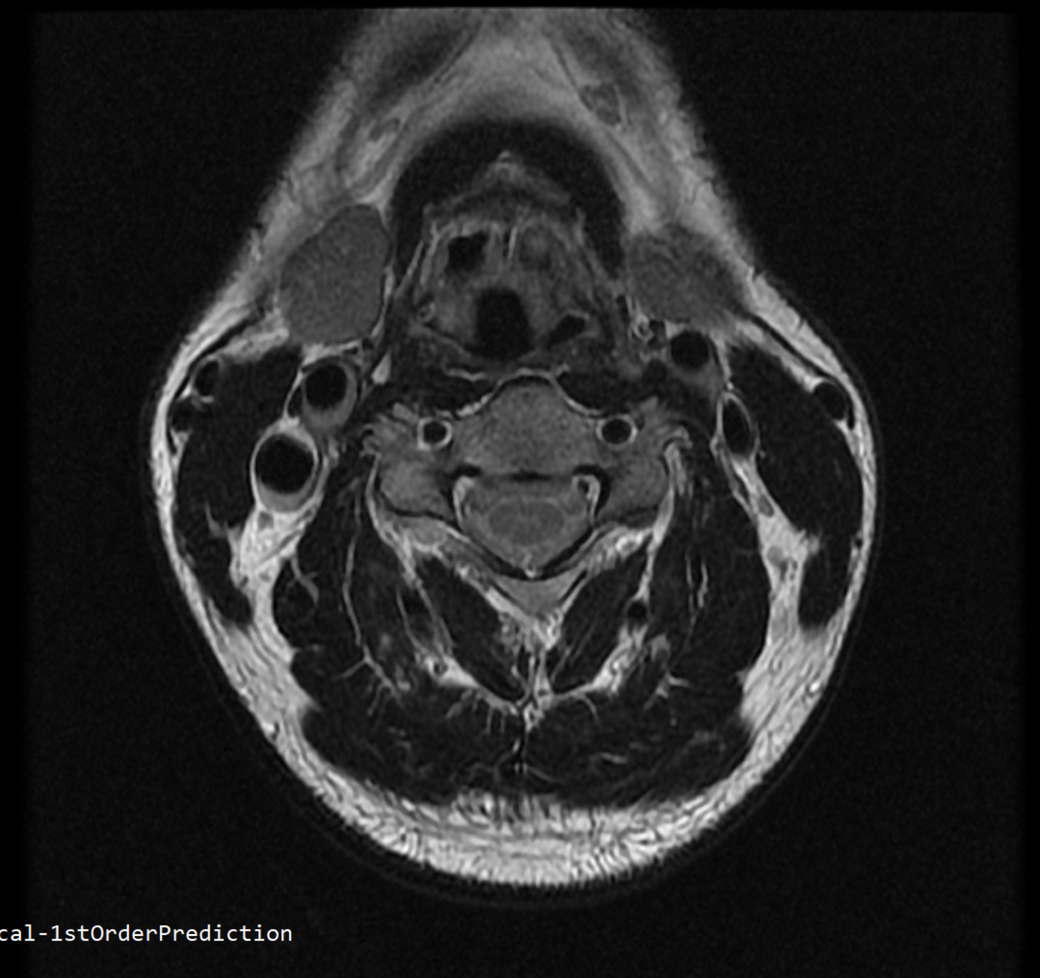

안녕하세요 목 경추 상단부터 순서대로 mri 촬영인데요

전체적으로 봐주시면 감사하겠습니다

• 2번 째 사진